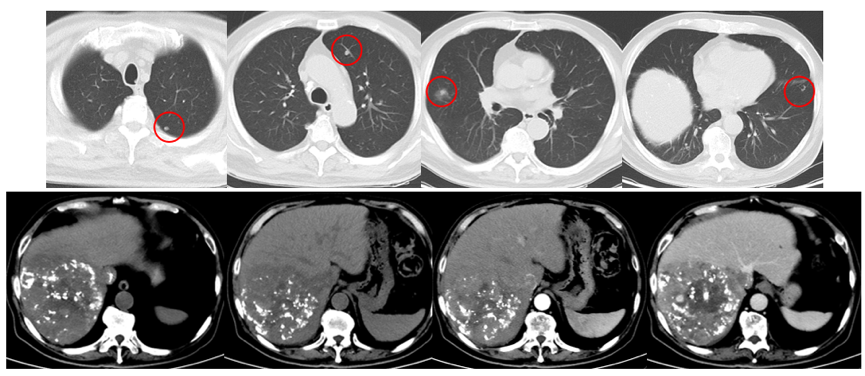

2021年3月8日复查AFP为>1210ng/ml;2021年3月8日复查CT提示,双肺转移双侧肾上腺转移;左侧肾上腺较前变小,但右侧肾上腺明显增大;右侧髂骨转移(图5)。

图5.2021年3月8日复查CT

2021年4月29日、2021年6月11日、2021年7月2日、2021年8月16日和2021年9月6日复查AFP分别为242ng/ml、11.93ng/ml、16.62ng/ml、52.61ng/ml和142.1ng/ml。2021年9月7日复查CT示,肺部病灶基本消失,双侧肾上腺病灶明显缩小(图7)。

图7.2021年9月7日复查CT

2021年10月18日AFP为443.9ng/ml。2021年10月20日复查CT示,肾上腺病灶较前明显增大,髂骨病灶缩小(图8)。

图8.2021年10月20日复查CT

2021年12月20日复查CT示,右侧肾上腺病灶明显缩小,髂骨病灶也进一步缩小(图9)。

图9.2021年12月20日复查CT

2022年2月8日复查CT提示,肺部病灶基本消失(图11),肾上腺病灶明显缩小,髂骨病灶进一步退缩(图12)。2022年2月9日AFP为411ng/ml。

图11.2022年2月8日复查胸部CT

图12.2022年2月8日复查CT